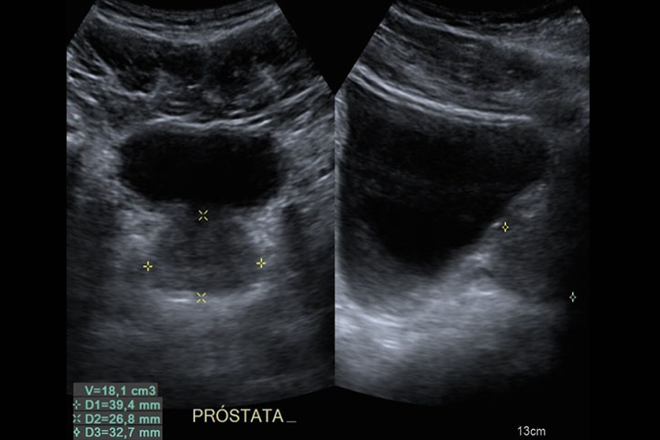

La próstata es una glándula del tamaño de una nuez (3 cm de diámetro) que pesa alrededor de 20 gramos y se encuentra únicamente en hombres. Está ubicada en la base de la vejiga y rodea la parte inicial de la uretra, el conducto que transporta la orina desde la vejiga hasta el pene.